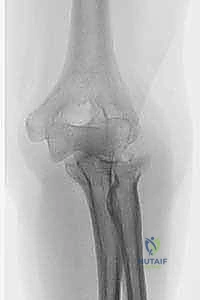

تحدث كسور رأس الكعبرة غالباً نتيجة السقوط على يد ممدودة (FOOSH - Fall On Outstretched Hand)، حيث تنتقل قوة السقوط من راحة اليد، عبر الساعد، لتصطدم بعنف في مفصل الكوع.

متى يصبح الكسر "معقداً" ويحتاج إلى استبدال؟

لا تحتاج جميع كسور رأس الكعبرة إلى استبدال. يصنف الأستاذ الدكتور محمد هطيف الحالات التي تستدعي هذا الإجراء المتقدم إلى:

* الكسور المفتتة بشدة (Comminuted Fractures): عندما ينكسر رأس الكعبرة إلى أكثر من ثلاث قطع صغيرة جداً لا يمكن تجميعها وتثبيتها بالمسامير.

* الثالوث الرهيب لمفصل الكوع (Terrible Triad of the Elbow): وهي إصابة كارثية تتضمن: خلع في مفصل الكوع، كسر في رأس الكعبرة، وكسر في الناتئ الإكليلي (Coronoid). في هذه الحالة، استبدال رأس الكعبرة ضروري لإنقاذ الكوع من الخلع المتكرر.